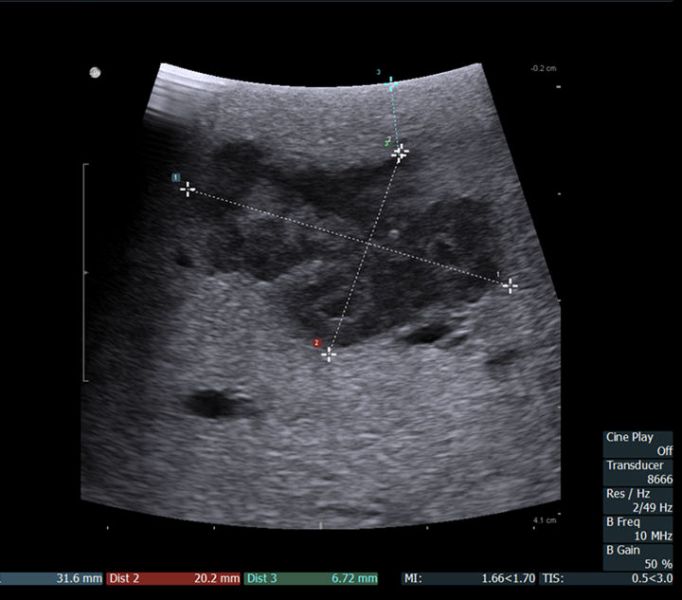

术中超声示肝VIII段肿块大小及距肝表面距离